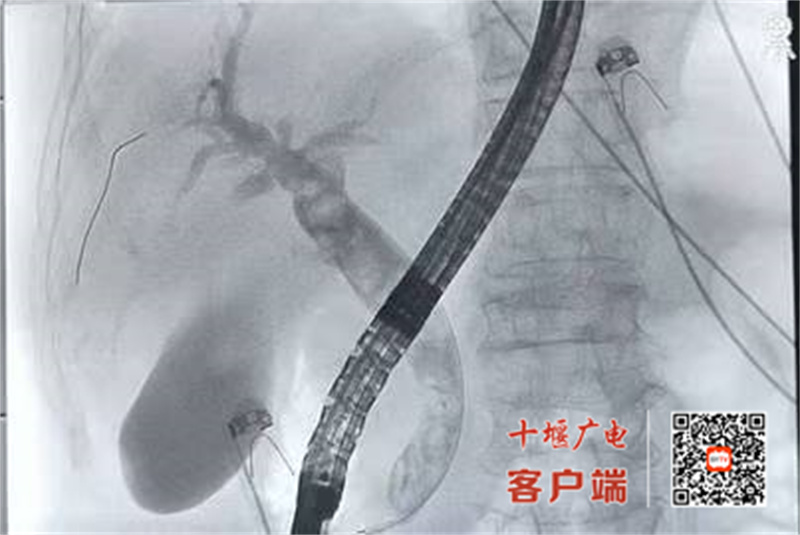

“我们当即决定采用ERCP这一‘超级微创’路径。”市中西医结合医院普外科主任曹扶胜介绍,ERCP手术经口腔、食管、胃自然腔道置入十二指肠镜,在X线监视下将导管导丝精准插入胆总管,完成造影、碎石、网篮取石,全程无切口、出血量不足5毫升,用时仅30分钟。

曹扶胜主任介绍,ERCP不仅可一次性清除胆总管结石,对胆总管狭窄、肿瘤所致阻塞性黄疸及医源性胆道损伤同样可行支架植入、扩张等治疗,具有可重复操作、住院时间短、费用低等优势。